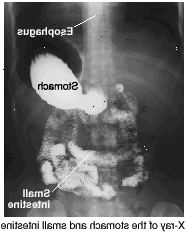

Horní GI série je x-ray zkouška z horní části zažívacího traktu (plocha z úst do začátku svého tenkého střeva). Tento test vám pomůže váš lékař najít nějaké problémy, jako jsou vředy, nádory, a některých chorob. K dispozici je malé množství záření s horním GI série. Ale výhody tohoto testu zdaleka převažují nad riziky.

Budete vyzváni k pití baryum (kapalné, který zvyšuje x-ray obrázků). Můžete také spolknout "fizzies," látka, která dělá vzduch se hromadí v žaludku. Nepoužívejte krkat, i když máte pocit, že se. Pro dosažení co nejlepších snímků, možná budete muset stát nebo ležet v různých pozicích. Když je čas, aby se na x-paprsky, budete vyzváni k zadržte dech na chvíli. Možná budete muset počkat krátce po zkoušce, aby se ujistil, že obrázky jsou čitelné.